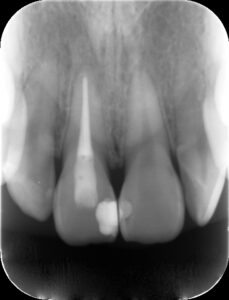

初診時レントゲン。上顎前歯の歯茎の腫れを主訴に来院。歯冠部に白い大きなレジン充填の跡が見られ、根尖部に黒いX線透過像を認める。